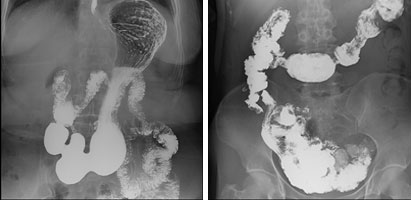

持续呈现高质量图像

Neo-Vision使用了多种检查方案独立设置的采集模式。可定制化的采集方案可以使采集时的X线曝光曲线及图像后处理更加的精准,图像清晰度更高。